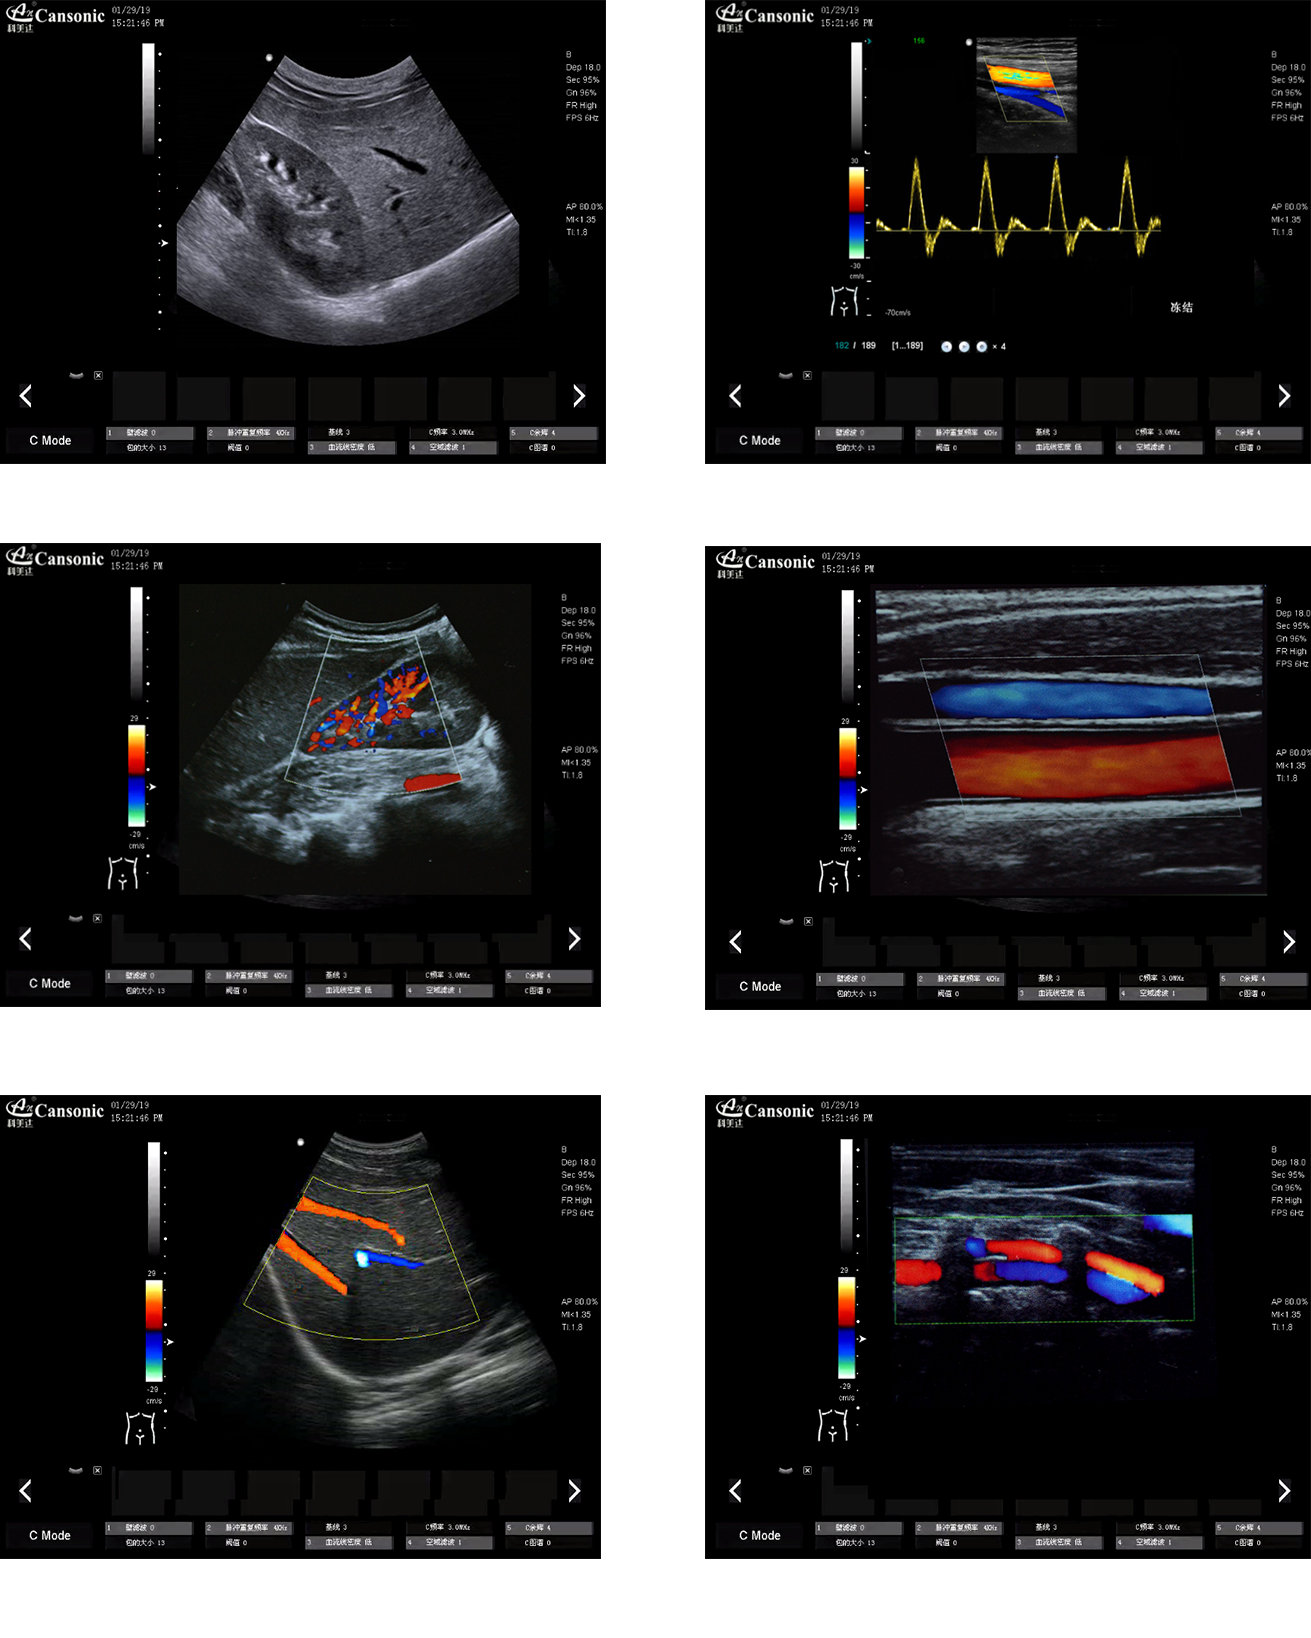

科美達K22圖像實例

1、全身應用型彩超,擁有完善的臨床應用解決方案

5、高分辨率灰階血流成像,提升對微細血管的血流探測靈敏度,對大血管管壁成像及管壁斑塊的診斷也有很大幫助